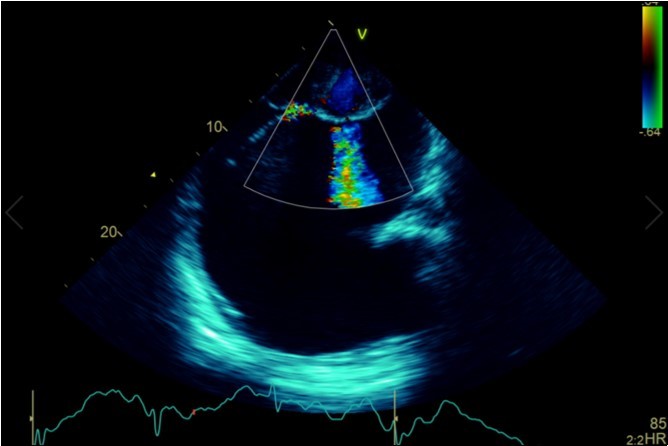

Figure 2b.Transthoracic echocardiogram Parasternal long axis view. Findings include severe mitral stenosis (‘hockey-stick’ appearance to mitral valves), raised left atrial pressure (interatrial septum fixed and bowed to right)

Transthoracic echocardiogram Parasternal long axis view. Findings include severe mitral stenosis (‘hockey-stick’ appearance to mitral valves), raised left atrial pressure (interatrial septum fixed and bowed to right)

A dramatically dilated left atrium was seen on a TTE (see Figure 2a, Figure 2b, Figure 2c, and Figure 2d). Severe mitral stenosis with associated regurgitation was evident, with a mean gradient across the valve of 11mmHg and a hyperdynamic left ventricle. The left atrial volume measured by Simpson’s biplane method (see Figure 2c) was 2108mL, or 1548.5 ml/m2, based on height 1.55 metres and weight 44 Kg. Normal left atrial volume in a woman is 16 - 34 ml/m21. The computed tomography scan (CT) chest AP view (see Figure 3) is also shown.